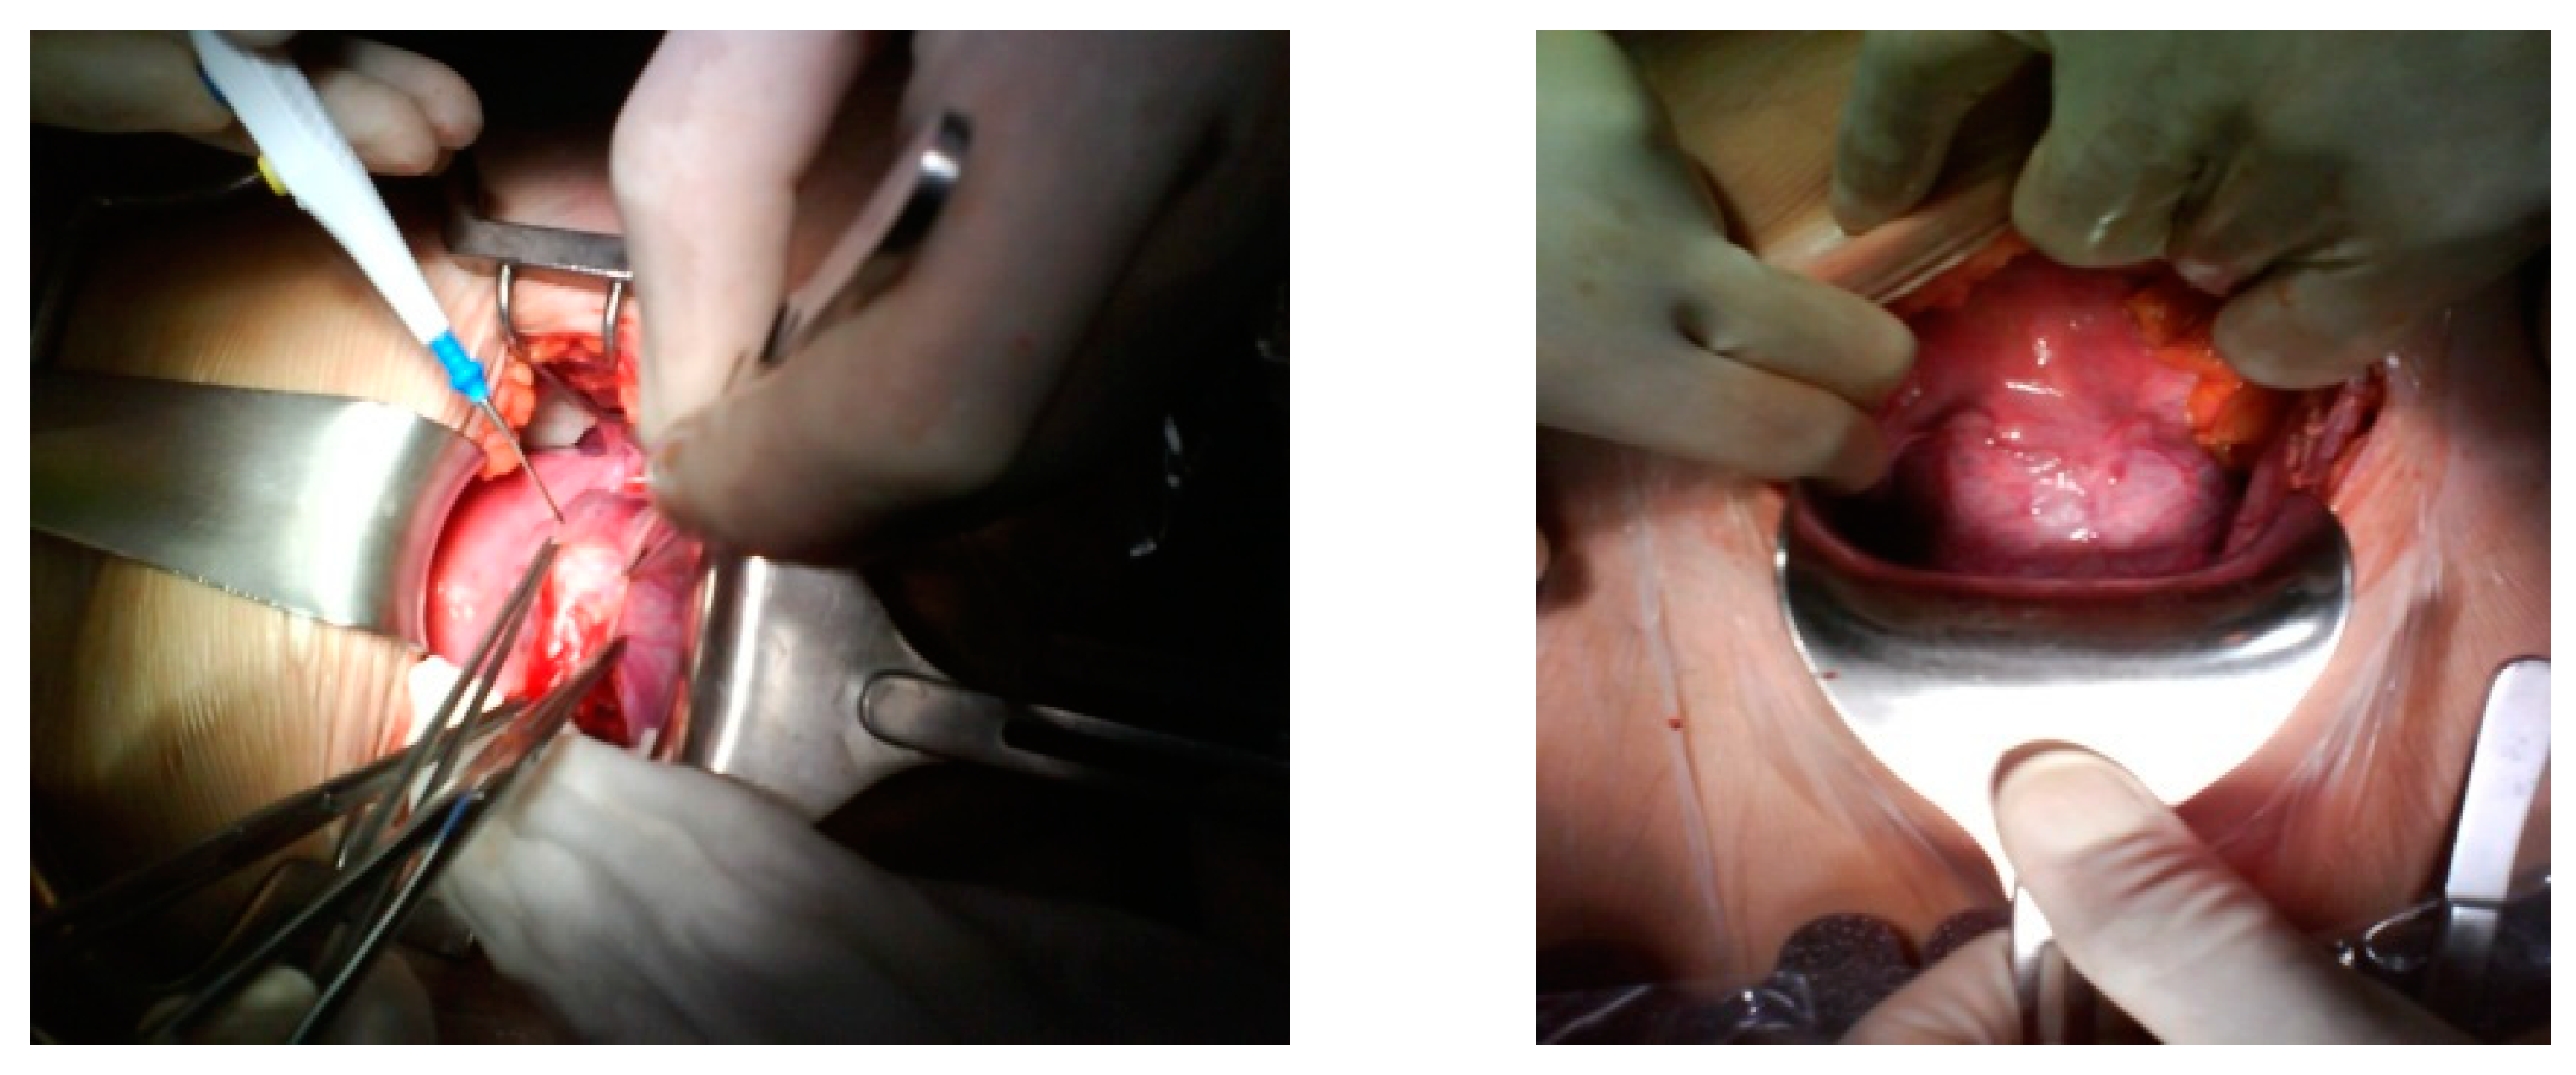

After discussion with the patient regarding the ultrasound findings, potential complications of the continuation of a cesarean scar pregnancy, and reproductive goals, the patient elected for permanent sterilization. She underwent an uncomplicated total laparoscopic hysterectomy with removal of the cesarean scar pregnancy. This is a definitive treatment for the resolution of the problem in a woman with her reproductive desire fulfilled. The risk and benefits of expectant management and the necessity of a series of follow-up visits were discussed with the patient and she decided definitive treatment because she had her reproductive desire fulfilled. Although our aim was to preserve the uterus, at the patient’s express wish, a hysterectomy was performed. During the surgery, when we separated the bladder from the uterus, the bulging of the gestational sac could be clearly identified in the scar area, with great vascularization (Figure 3). The uterus did not show any other abnormal finding. The patient was discharged on the third day following surgery without complications and was scheduled for close follow-up with obstetrics and gynecology.

Figure 3. The bladder was released from a gestational sac.